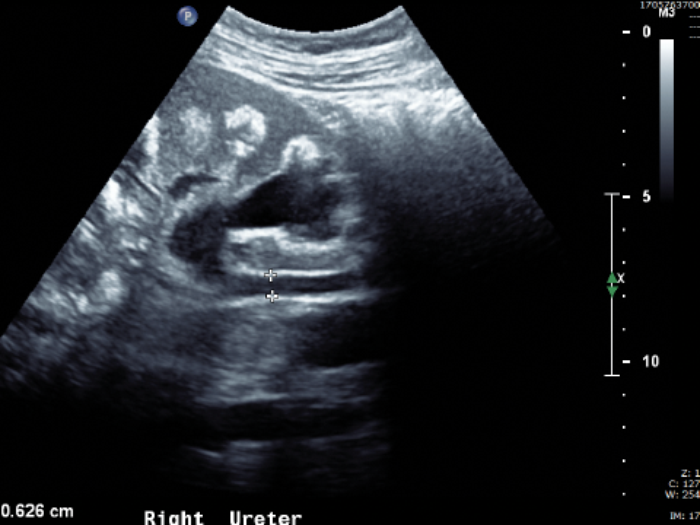

The patient from Case 1 presents as an emergency with right loin pain and has an ultrasound performed (Figure A).

- What does this ultrasound show?

-

Right hydroureter and hydronephrosis. Calcification with medullary shadowing. |